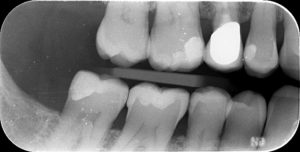

Publié le 06/12/2017Un patient âgé de 50 ans sans pathologie particulière se présente dans notre cabinet pour un contrôle périodique ; la radio révèle une lésion carieuse en distal de la 45.